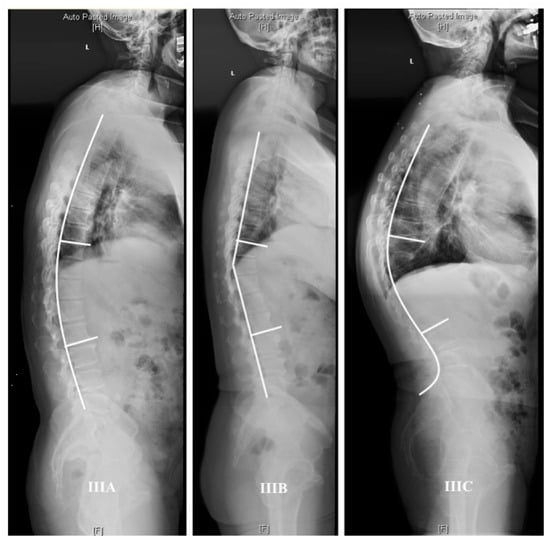

4.2. Thoracolumbar Junctional Kyphosis